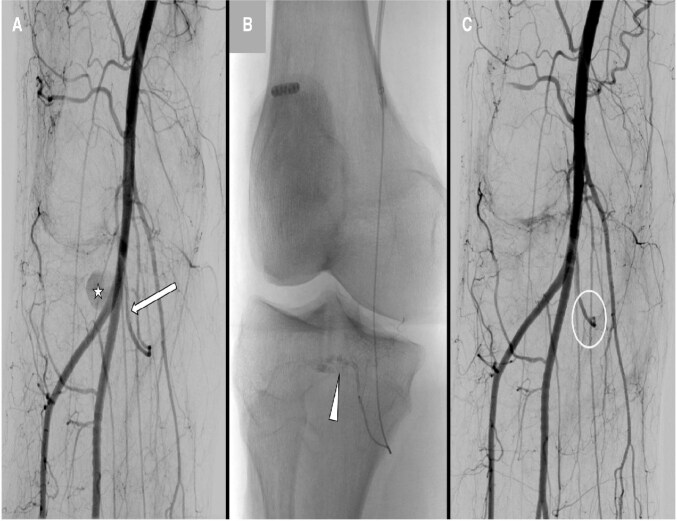

前交叉韧带(ACL)断裂是一种常见的膝关节损伤,通过关节镜重建因其安全性和低并发症发生率(约1%)而广受欢迎。这种手术造成的血管损伤极为罕见,发生率为0.003%-1%。膝关节镜检查后的假性动脉瘤更不常见。本文讨论一例罕见的假性动脉瘤重建后,在右膝内侧间动脉(IMGA)的关节分支,起源于胫骨前动脉高起点。一名47岁的血管性血友病患者在acl重建后30天出现了24毫米的假性动脉瘤。ct血管造影显示假性动脉瘤靠近胫骨隧道螺钉和异常高的胫骨前动脉起源。急诊血管造影证实了这一点,使用Squid Peri 18栓塞成功,无并发症。病人恢复得很好。血管损伤是一种罕见的膝关节镜并发症,但早期诊断和解剖变异的认识是必不可少的。医源性假性动脉瘤的血管内治疗安全有效,且恢复迅速。

Rupture of the anterior cruciate ligament (ACL) is a common knee injury, and reconstruction via arthroscopy is popular for its safety and low complication rate, around 1%. Vascular injuries from this procedure are extremely rare, with an incidence of 0.003%-1%. Pseudoaneurysms following knee arthroscopy are even less frequent. This paper discusses a rare case of pseudoaneurysm after ACL reconstruction in the articular branch of the right inferomedial genicular artery (IMGA), originating from an anterior tibial artery with a high origin. A 47-year-old man with Von Willebrand disease developed a 24 mm pseudoaneurysm 30 days post-ACL reconstruction. CT-angiography showed the pseudoaneurysm near the tibial tunnel screw and an unusually high anterior tibial artery origin. Emergency angiography confirmed this, and embolization using Squid Peri 18 was successful, with no complications. The patient recovered well. Vascular injury is a rare knee arthroscopy complication, but early diagnosis and awareness of anatomical variations are essential. Endovascular treatment for iatrogenic pseudoaneurysms is safe and effective and facilitates rapid recovery.